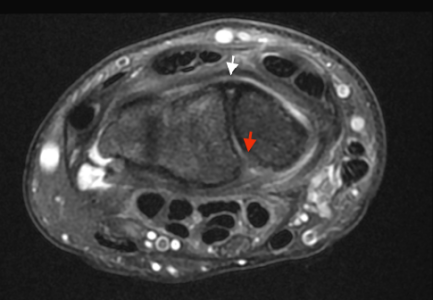

Le ligament scapho-triquetral palmaire est un ligament des articulations du carpe (poignet).

Il relie le scaphoïde au triquétrum en passant au-dessus du lunatum sans s'y insérer.

Il participe indirectement à la stabilité scapho-lunaire.